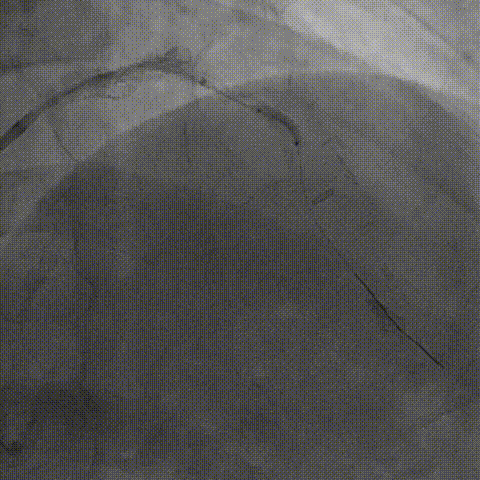

病变部位旋磨后,振波后超声对比